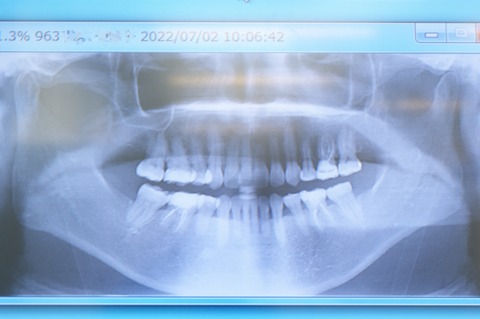

約5年前にお口全体の矯正治療をした後、必要な補綴及び咬合処置をして終了した患者さんが、6回目の定期検診でいらしたときのパノラマⅩ線写真です。(53歳、女性)

矯正前は顎の大きさに比して歯が多すぎるため、林立して歯を支える歯槽骨が不均等であるのに比べ、矯正後は歯が適当な間隔を保って位置し、結果歯槽骨が均等に歯を支えている様子が確認できます。

これこそ、矯正治療が歯の健康に貢献する大きな要点の一つなのです。